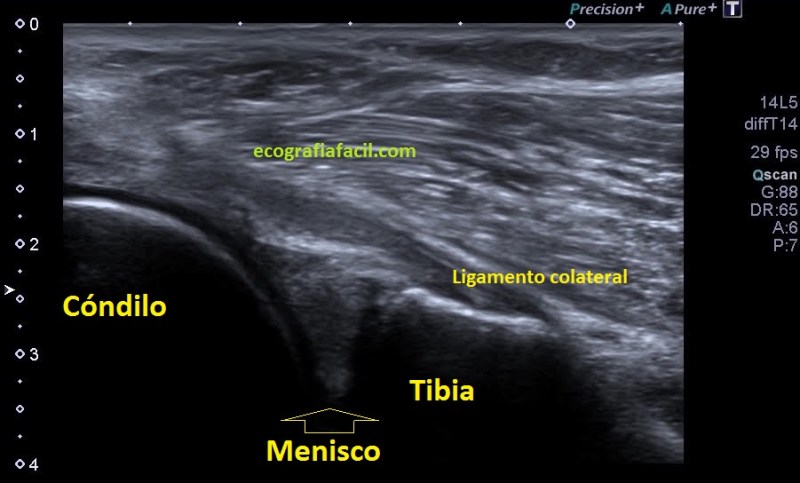

La afectación del menisco es variable, por supuesto, verás muchos que difieran de la normalidad. En la imagen 2 has visto un menisco afectado, en la imagen 3 vas a ver otro, mira:

3

En la imagen 3 puedes ver un menisco que en su parte central tiene una línea hipoecogénica, bastante sutil, fíjate bien, irregular que lo divide en 2 partes. Pero ¿qué pasa cuando un menisco está dañado? Cuando un menisco por sobreuso, sobrepeso o la razón que sea pueden mostrar cambios en la ecoestructura, ya sea por que se han fisurado, como el de la imagen 2, incluso pueden llegar a romperse. Es fisura o rotura puede ser la vía de escape del líquido intraarticular de la rodilla hacia la parte extraarticular y si eso se produce, podemos encontrarnos con esto:

4

El líquido ya se ha salido y ha formado una bolsa situada superficial al menisco, profundo al ligamento colateral y que está señalado con flecha amarilla. Marcadamente anecoico puedes verlo en tamaños variables en función el alcance del líquido que haya salido y en función de las variantes propias de cada paciente.